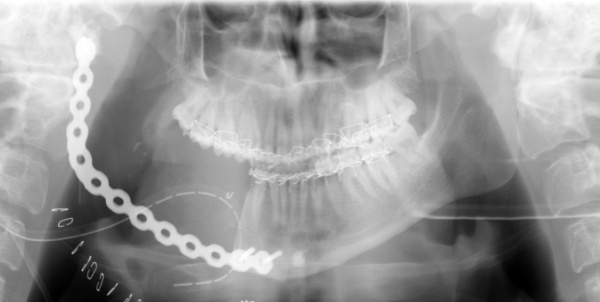

Wir führten zunächst eine Zystektomie in Intubationsnarkose unter Erhalt des N. alveolaris inferior durch. Die histologische Untersuchung ergab ein Ameloblastom. Daraufhin erfolgte eine Hemimandibulektomie rechts von extraoral mit Erhalt des rechten Unterkieferköpfchens und Überbrückung des Defektes mit einer Rekonstruktionsplatte. (Abbildung 4). Histologisch fanden sich intraossär und in der anteilig resezierten Mundschleimhaut weitere Ausläufer des Tumors. Die Resektionsränder waren tumorfrei.

Drei Monate Später wurde die rechte Unterkieferhälfte mit einem freien Rippen- und Beckenkammtransplantat rekonstruiert.

Da der die Zyste begrenzende Knochen teils extrem ausgedünnt war, erfolgten eine Unterkieferteilresektion und im gleichen Eingriff die Rekonstruktion mit einem mikrochirurgisch reanastomosierten Beckenkammtransplantat (Abbildung 8).